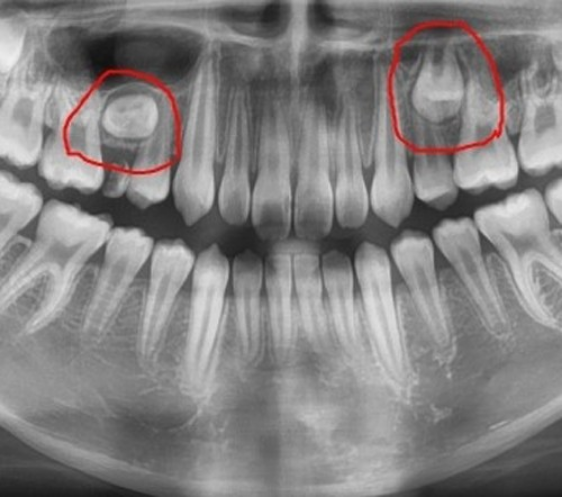

세 번째로, 조기 맹출 치아라는 이상이 있습니다. 신생아가 아직 어린데에도 불구하고 치아가 이상하게 발육하여 이를 조기에 뽑아야 할 수도 있습니다. 조기 맹출 치아는 신생아의 입안에서 발견되는 가장 흔한 치아 이상 중 하나이며, 적시에 적절한 치료를 받아야 합니다.

신생아에게 나타나는 치아 종류 중 하나인 조기 맹출 치아는 어떤 원인으로 발생할까요? 일반적으로 조기 맹출 치아는 유전적 요인, 태아기 발달 이상, 혈액순환 문제 등 다양한 이유로 발생할 수 있습니다. 예를 들어, 태아기 발달 이상으로 인해 치아가 조기로 발생하거나, 유전적인 요인으로 인해 치아가 이른 시기에 나타날 수 있습니다. 또한, 혈액순환 문제로 인해 치아가 조기에 발생할 수도 있습니다. 이러한 이유들로 인해 조기 맹출 치아가 발생할 수 있으며, 이는 신생아의 구개 뼈에 영향을 줄 수 있습니다.

조기 맹출 치아가 발생했을 때 대처법은 무엇일까요? 가장 중요한 것은 전문가의 진단과 조언을 받는 것입니다. 조기 맹출 치아는 신생아의 건강에 영향을 줄 수 있기 때문에 즉시 치과 전문의를 찾아 상담하는 것이 중요합니다. 또한, 조기 맹출 치아가 발생한 경우 신생아의 영양 상태와 구개 뼈 발달을 고려하여 적절한 치료 방법을 결정해야 합니다. 이를 통해 조기 맹출 치아로 인한 문제를 최소화하고 건강한 구개 뼈 발달을 도울 수 있습니다.